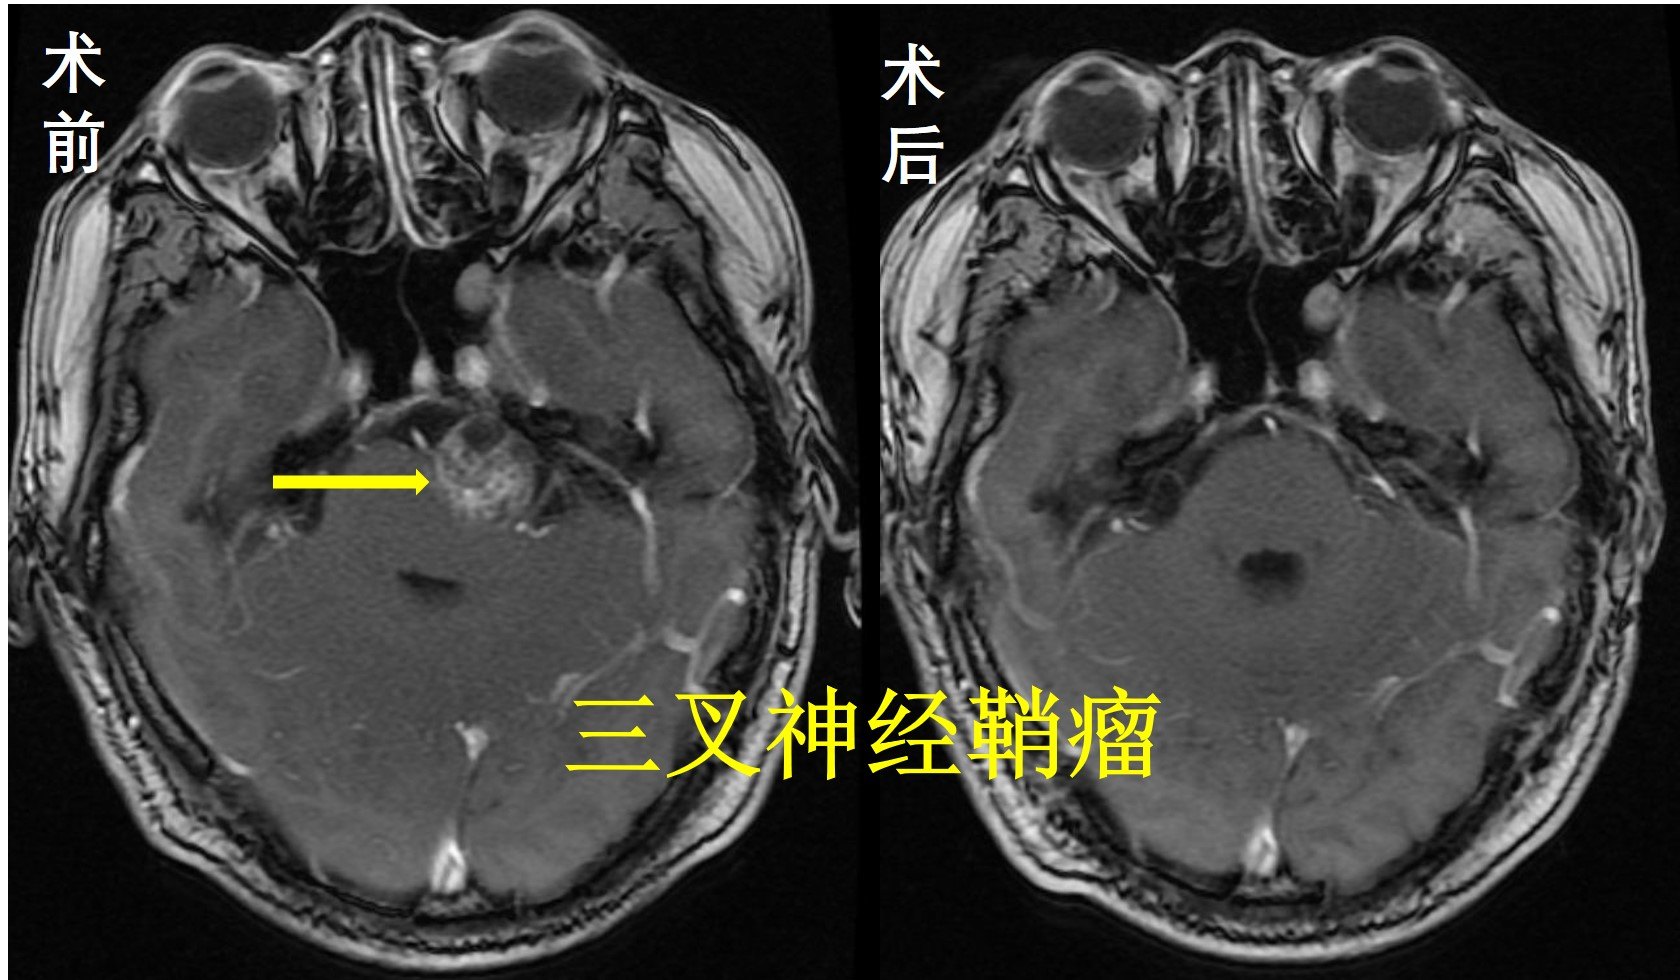

脑深部肿瘤的外科治疗

位于脑部表浅的肿瘤治疗效果相对较好,而位于脑干、功能区域、颅底及脑深部肿瘤,手术难度大,致死致残率高,并发症和后遗症也较多,如何能安全切除肿瘤且最大程度保留神经功能,让患者生活质量得到改善,一直是神经外科医生面临的挑战。

复旦大学附属肿瘤医院神经外科团队一直致力于深部脑肿瘤的外科治疗,积累了丰富的经验,同时引进高端仪器设备(荧光显微镜、神经内镜、神经导航、术中超声等)辅助,运用熟练的显微神经外科技巧,让来自全国各地的脑肿瘤患者得到了有效的治疗,效果显著。